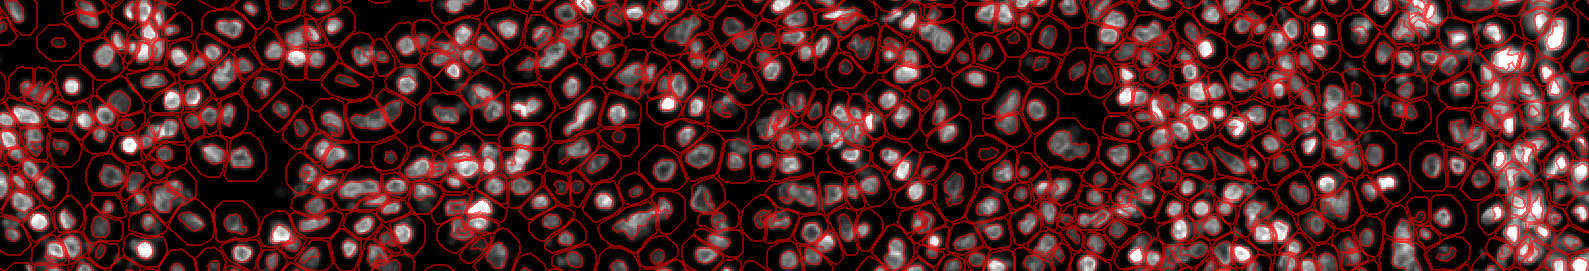

On an image with a clean staining, we can very quickly get a decent result with the basic QuPath built-in method, but what about a case with a more diffuse staining?

- Following the same steps as in Ex 5.1.1 Mean nucleus-to-cytoplasm CD73 intensity, try to segment the nuclei in images of mouse spleen.

- We just want to count them, so you don't have to make any intensity measurement in them.

- Using the steps that we saw before, try to segment the nuclei the best that you can.

- If you are having a hard time finding parameters, you can start from these: